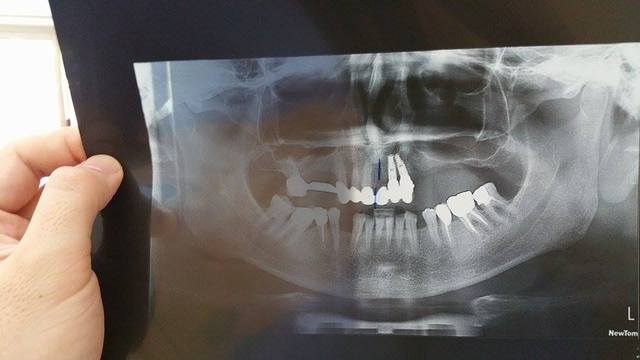

Pour finir voila le cas d'un patient (médecin généraliste que j'ai eu en consult hier).

Il vient me voir pour une douleur en bas à droite et un bridge maxillaire récent qui s est cassé .

Un devis dans notre cabinet lui avait été remis pour faire de la prothèse combinée.

Il est parti dans un "pays européen se faire poser " cette merde sans nom et certains de ses implants ont échoués.(pas deux interventions gratuites).

Au final , il finit avec une prothèse combinée , et avoir payer plus cher pour de la merde.

Voila les mentalités actuelles.